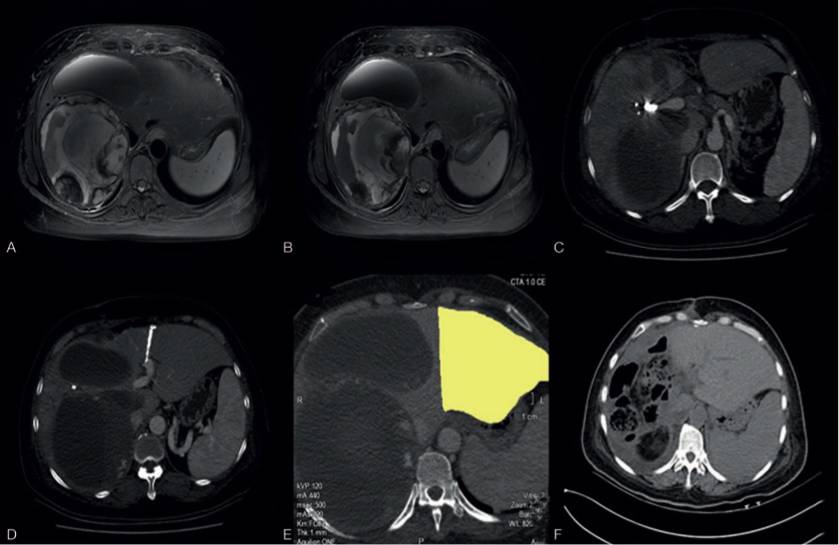

9、一例经皮微波消融肝实质分隔联合门静脉栓塞计划性巨大胃肠间质瘤肝转移切除

Liu J, Zhang C, Chen Y, et al.

Department of Pathology, Zhejiang Provincial People’s Hospital, People’s hospital of Hangzhou Medical College,China

Medicine (Baltimore). 2017Oct;96(42):e8271.

患者女性,44岁,4年前因十二指肠GIST行胰十二指肠切除术,诊断高度复发风险GIST,因经济状况术后未接受伊马替尼辅助治疗,术后2年发现肝转移,MR显示肝多发转移分布于几乎全部肝段(除外肝左外叶),最大病灶10x12cm,口服伊马替尼治疗后病灶稳定,拟行手术切除,但残余肝体积不足,行经皮微波消融肝实质分隔联合门静脉栓塞治疗,10天内残余肝体积由34%提高至50%,随后成功施行肝右三叶切除术,病理显示GIST(梭形细胞型),CD117与DOG-1阳性,核分裂像10/50HPF,术后继续伊马替尼辅助治疗,随访17个月未见复发。

毫无疑问,该例病例从为GIST巨大肝转移负荷拟行手术切除的患者提供了技术路线,从近期随访看也为患者带来了更多的生存获益,该技术更早用于肠癌肝转移的手术治疗;该病例除了技术性之外,更多的思考还是在GIST肝转移切除观念能否成功移植肠癌肝转移成功的理念,尽管现阶段仍缺乏前瞻性的对照研究(日本有一项例数极少的报道),但笔者仍认为是可行的,一是由于的确存在较多终生不发生肝外转移的GIST患者,二是由于伊马替尼卓越的肿瘤控制,但病例选择依旧需要参照肠癌肝转移中生物学行为是否可切除的理念,除了TKI治疗有效之外,本病例缺乏的基因检测是十分重要的,不同的基因突变类型对TKI疗效存在的差异以及PFS的差异均影响这肝转移手术的适应人群筛选与手术时机的界定。